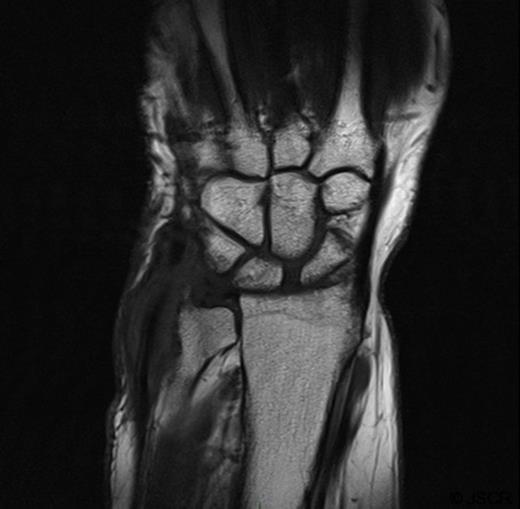

The patient agreed to a repeat biopsy and excision of the necrotic bone (Figure 4). Microscopy of the specimen again showed a florid granulomatous inflammatory process with areas of fibrinoid necrosis. Cultures isolated Mycobacterium tuberculosis.

Post-operative Xray of the wrist showing excision of the ulnar styloid